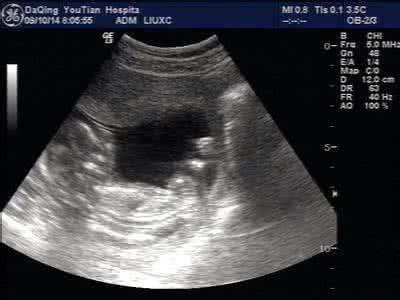

大家都知道,除了特殊原因外,医院是禁止使用B超验宝宝性别的,也不会告诉孕妇相关信息,怀孕期间孕妇都会做几次B超,其实如果我们想知道腹中宝宝的性别,通过B超单子就可以辨别出来了!

1.一般来说,如果肚子里的是女宝,B超单子上就会看到三条线,如果腹中是男宝的话,单子上就会出现三个点+小丁丁。

2.也有通过以下两点信息看出腹中宝宝的性别:胎囊的大小,如果胎囊的大小宽度相差不大,那么可能就是女孩,如果胎囊长宽相差一倍以上,也许就是男孩了;还有就是看双顶径和股骨长,头大腿短的一般是男孩,头和腿的相差小于二则是女宝宝。